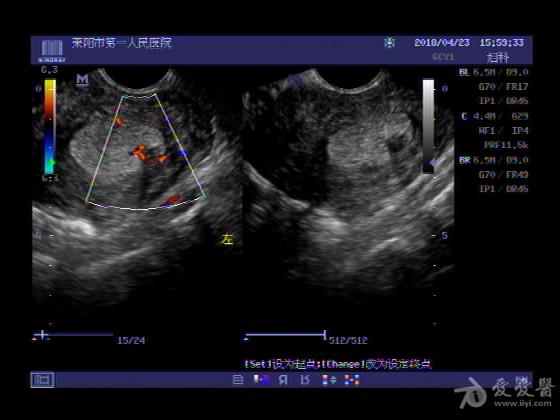

女,48岁,月经量多,两个月,一年前出现过类似现象,刮宫吃药后缓解。

超声可见:子宫内膜显著增厚,后肌壁内膜可见范围约3.27X0.90CM低回声区,CDFI显示较丰富线样血流,宫底宫腔内见类**状低回声结节。前肌壁见多发类圆形低回声结节。

超声提示:子宫内膜增厚(建议刮宫病理),子宫多发肌瘤

病理结果:内膜增生